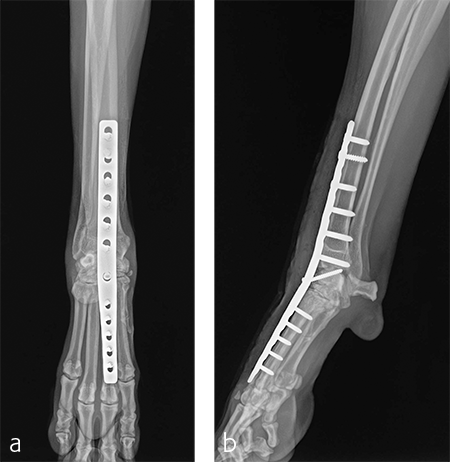

A custom fiberglass palmar splint was applied from the paw to just distal to the elbow after surgery. The splint was used for 4 weeks followed by a soft padded bandage for 4 weeks. Bandage changes were performed weekly. Activity was restricted to leash walks only for 12 weeks postoperatively. Radiographic examination 8 weeks after surgery revealed early healing of the pancarpal arthrodesis and stable implants. No complications were noted (Fig 6).

The patient was returned to normal activity 4 months after surgery. Radiographic examinations at 6 and 6.5 months after surgery revealed stable implants and fusion of the carpus (Fig 7 and 8). Functional outcome was excellent 1 year postoperatively. The patient had returned to full weight-bearing without lameness and the carpus was pain-free and stable.

Immediate postoperative images confirmed anatomic alignment and adequate carpal extension (Fig 10). At the 11-week postoperative follow-up examination, functional recovery was very good with images revealing stable implants and healing of the arthrodesis (Fig 11). The dog was then allowed to return to normal activity.